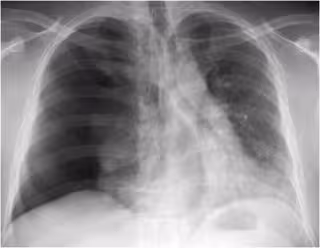

"El diagnóstico del neumotórax es eminentemente radiológico. El paciente suele acudir a consulta con dolor torácico y dificultad para respirar. Es conveniente realizar una radiografía en espiración para diferenciarlo de otras entidades. En casos más graves es necesario someter al paciente a cirugía que restablezca la funcionalidad del pulmón afectado", ha zanjado el experto.